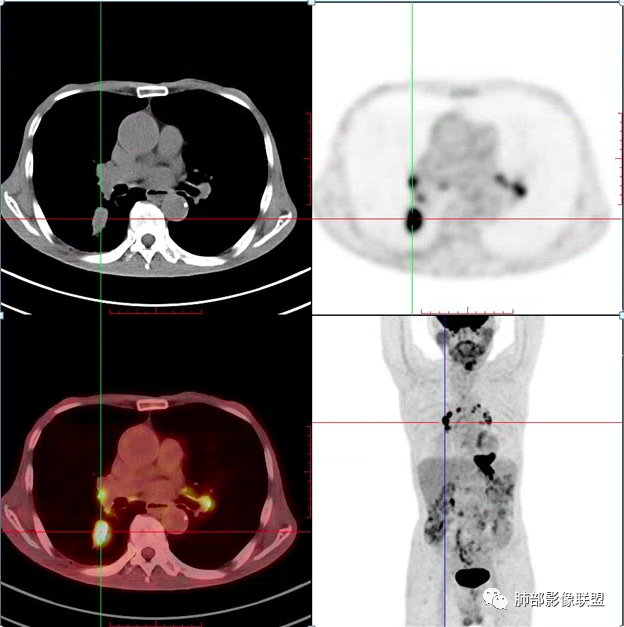

老年男性患者,胸部隐痛1月入院,有长期吸烟史,胸部CT:右肺下叶背段梭型结节灶,边界清晰,无明显分叶、毛刺及周边磨玻璃影,内部密度不均匀,支气管截断,增强扫描不均匀轻度强化,内部似乎见支气管黏液栓,纵隔淋巴结不大,考虑恶性病变:小细胞癌(缺少典型的纵隔肺门淋巴结增大融合),鳞癌(病史复合,但没有阻塞性肺炎,内部没有坏死,),类癌(多见于女性患者,与吸烟关系不大),首先考虑典型类癌,

老年男性,右肺下叶梭形或椭圆形结节,形态较规则,边缘光整,支气管截断,增强不均匀轻度强化,右肺门及纵隔淋巴结增大,考虑恶性病变,鳞癌或小细胞癌,神经内分泌癌(小细胞形)。

老年男性患者,右肺下叶背段梭形结节影,边界比较光整,密度均匀,没有明显的分叶毛刺,没有阻塞性肺炎的表现,这些感觉具备有良性的特点。而近端支气管截断,增强明显的强化,纵隔多发的淋巴结,显得是恶性的特点。总体印象,老年患者+支气管截断征象+明显强化的结节+纵隔多发淋巴结,还是考虑恶性结节,小细胞癌或是鳞癌。

男性,老年人,长期吸烟史,老慢支背景,右下肺背段占位,支气管亚段门口堵,病灶长轴与支气管平行,推测腔内生长可能,病灶内血管穿行,周围干净,轻度强化,右肺门淋巴结肿大,考虑恶性,神经内分泌癌(大小类)>淋巴上皮瘤样癌>腺癌>鳞癌

右肺下叶梭形实性结节,密度均匀,边缘光整,局部膨隆,近端支气管截断,轻度强化,血管走行自然,右肺门及纵隔淋巴结增大,考虑小细胞癌>鳞癌

右肺下叶背段结节,沿着支气管走行呈长椭圆形,边缘圆滑清晰,近端支气管阻塞,远端支气管有沿壁增厚,右肺门淋巴结肿大,中度强化,老年男性,吸烟病史,肺气肿背景,考虑小细胞肺癌,鉴别鳞癌

老年男性,吸烟史,右肺下叶梭形肿块,边缘平直有分叶,支气管近端阻塞,右肺门肿大淋巴结,增强后轻度强化,欠均匀,首先考虑恶性,小细胞肺癌?

老年男性+吸烟+右下肺肿块影+支气管截断+淋巴结肿大,考虑恶性,倾向小

老年男性,吸烟史,右肺下叶背段梭型软组织肿块,边缘膨隆,不均匀强化,近端支气管截断,同侧肺门及纵隔淋巴结肿大,支持恶性,小细胞可能大,鳞癌缺少阻塞性改变

晨读,右下叶梭形占位,边界光滑,支气管截断,可见尾征,不均匀轻度强化,肺门淋巴结肿大,有吸烟史,高龄高危患者,首先考虑恶性,考虑小细胞癌,鉴别一下鳞癌

老年男性,前胸隐痛1月。2年前有白内障手术史。右下肺结节,沿中轴呈梭形,膨隆,边清、无分叶,无毛刺,近端支气管截断完全堵塞,病灶以远未见阻塞性炎症及肺不张。内部密度基本均匀,增强轻微强化,似见局部低密度影。纵隔及右肺门见肿大淋巴结。整体考虑恶性可能性大,小细胞癌?鳞癌?注意鉴别良性结节—错构瘤。

老年男性,长期吸烟史,右肺下叶背段梭形低密度灶,边界清晰,无明显分叶、毛刺,边缘稍彭隆,支气管截断,右肺门淋巴结增大,增强扫描不均匀轻度强化(延迟略明显),首先考虑恶性,小?不典型结核球待排。

右肺下叶背段结节,气管堵塞,密度均匀,边界清晰,无明显分叶、毛刺,边缘膨隆,右肺门淋巴结增大,增强轻度强化,考虑小细胞癌,鉴别鳞癌。

右肺下叶梭形软组织结节,密度均匀,明显尾巴,边缘光整,近端支气管截断,轻度强化,血管走行自然,又腊肠尾巴征象

考虑恶性  小细胞癌?

男,83,前胸部隐痛不适1月。有长年大量吸烟史。胸部CT:肺气肿,右肺下叶纺锤型实性结节灶,边界清晰,支气管截断,内部密度不均匀,增强扫描不均匀强化,右肺门淋巴结大。考虑恶性病变:小?鳞?鉴别炎性肉芽肿、错构瘤等。

晨读:老年男性+吸烟+右肺下叶与气管长轴一致的梭形肿块影+支气管截断,轻度强化,右肺门肿大淋巴结,考虑恶性,小细胞肺癌可能,鉴别鳞癌

呈典型管状改变,近端支气管堵塞、稍扩张,病灶有强化倾向于恶性,没有强化倾向于炎性病变(结核之类);近端呈结节状(鳞癌多一些),这个病例呈管状(小细胞Ca多一些);平扫与强化有差异,有轻度强化,是粘液栓还是血管?

病理结果:小细胞肺癌